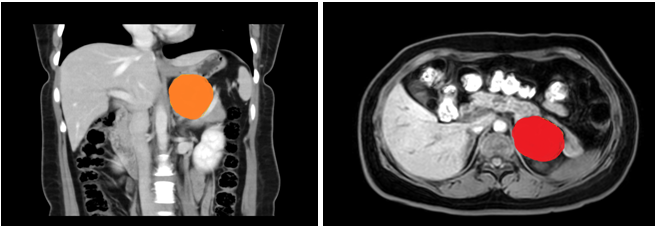

患者,女性,35岁,在五楼自拍 上腹部CT增强示:左侧腹膜后囊性病变,支气管囊肿不除外;入院后上腹部MRI平扫+DWI+增强扫描+MRCP示:左侧肾上腺上方囊性病变,考虑来源腹膜后间隙,1)支气管源性囊肿2)淋巴管囊肿可能,建议复查。

在张煜副主任带领下,经过肝胆外科全科细致讨论,认为占位较大,位置靠后,微创难度大,需完善相关检查,精细术前准备。经过医护一体化管理,打消了患者的术前顾虑,在全麻下行腹腔镜下腹膜后囊性占位手术+广泛腹腔粘连松解术,手术顺利,术后病理结果为良性,患者术后一周内顺利出院。患者表示,术后经过了解,得知此例手术难度较大,目前恢复良好,特意送来锦旗表达感谢。